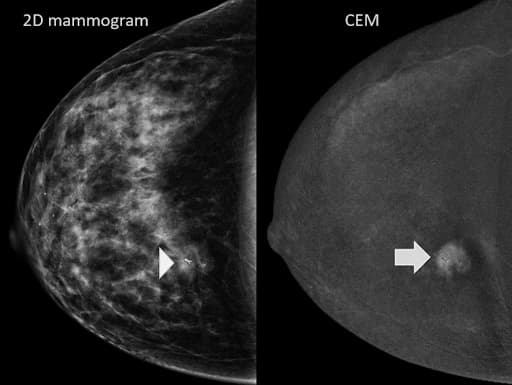

On the left is a standard 2D mammogram – the breast tissue appears dense, and the cancer is barely visible (indicated by the arrowhead). On the right is a contrast-enhanced mammogram of the same breast, which clearly outlines the cancer's size and shape and confirms it's the only tumor present (arrow).

Photo Courtesy of MD Anderson